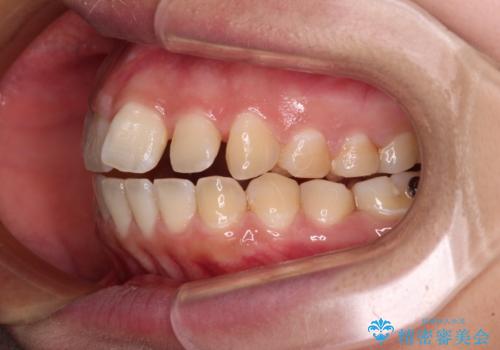

- 上下の前歯が非接触であることと、それに伴う口元の閉じにくさを気にして来院された患者様です。

奥歯の咬み合わせを見ると、上顎が下顎に対して相対的に前方にありました。

口元の閉じにくさを改善するためには、上顎臼歯を後方に移動させた咬み合わせにする必要があります。

インビザライン単体で改善することも可能ですが、達成する可能性が高くないため、カリエールディスタライザーという補助装置を併用して、より確実性を上げることとしました。

奥歯の咬み合わせを改善しながら、並行してインビザラインで歯列を整えることとしました。